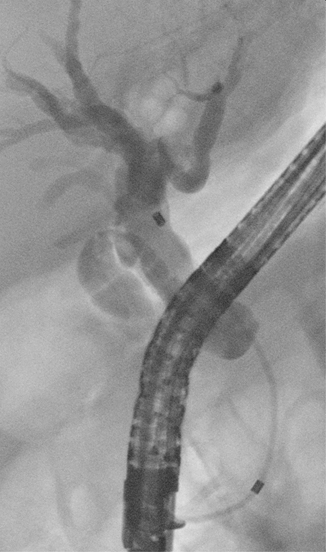

Fig. 8.5

Occlusive cholangiography showing complete transection of the common bile duct with multiple metal clips placed during laparoscopic cholecystectomy (Bergman type D lesion of the common bile duct)